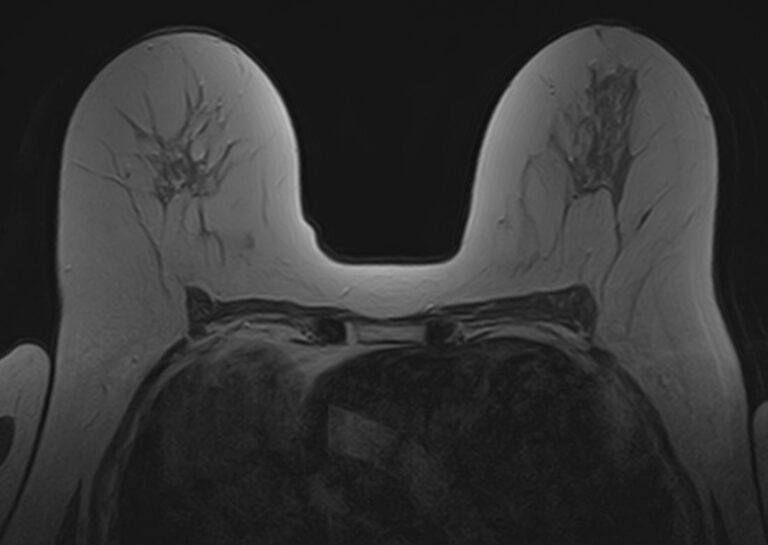

- Для оценки состояния силиконовых имплантов после пластики груди;

Выполнение МРТ молочных желез без контрастирования возможно для динамического наблюдения состояния имплантатов после пластической операции груди. Во всех остальных случаях во время проведения исследования внутривенно вводится контрастное вещество. Для контрастного усиления применяются препараты на основе солей гадолиния (Магневист, Гадовист и др).